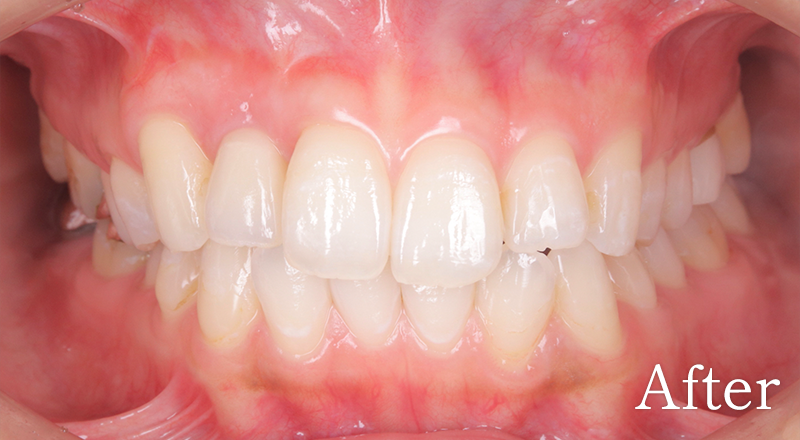

CASE5

骨格3級患者に対し、臼歯部にインプラント治療を行い咬合回復を行なった1症例

マークをスライドしてご覧ください

インプラント症例7

主訴 噛もうとすると受け口になってしまう

治療内容 下顎臼歯部インプラント、咬合再構成、セラミック治療

治療期間 約1年

費用 診断料:22万円(税込)

下顎顎臼歯部インプラント埋入手術:22万円(税込)×1本

セラミック補綴:22万円(税込)×1本

セラミック治療:11万円(税込)×23本